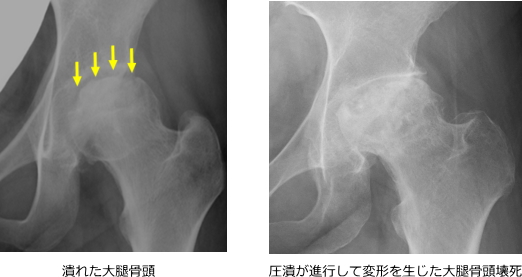

大腿骨頭(股関節の球状の骨)への血流が低下・途絶することで骨が壊死し、潰れてしまう病気です。

壊死の範囲が広がると股関節の形が変形し、強い痛みを生じます。

初期はレントゲンで異常が見えにくいため、MRI検査が有効です。

壊死の範囲が大きいほど進行リスクが高くなります。